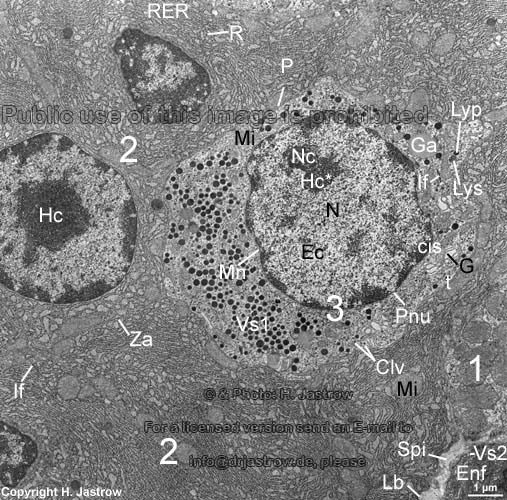

Enterochromaffine Zelle des Magens der Ratte (Für unbeschriftetes Originalbild bitte hier klicken !)

1 = benachbarte Belegzellen (bilden Salzsäure und den Intrinsic-Factor zur Resorption von Vitamin B12);

2 = Hauptzellen (bilden Pepsinogen, Lipasen und Kathepsin);

3 = enterochromaffine G-Zelle (bildet Gastrin); Clv = clathrinüberzogene Endozytosevesikel;

Ec = Euchromatin (hier findet die Transkription [Ablesen der Erbinformation + Synthese der m-RNA] statt);

Enf = Endotheliocytus nonfenestratus (mit Vesicula secreta Vs2 im Cytoplasma, die der Cytopempsis dienen);

G = Golgi-Apparat, mit cis-Seite[Aufnahme-Seite]; hier treten vom endoplasmatischen Retikulum abgeschnürte

Bläschen an das Golgi-Feld heran, und t = trans-Seite [Abgabeseite], hier schnüren sich reife Sekretvesikel ab;

Ga = Gutta adipis (Fetttropfen); Hc = Heterochromatin (inaktive Abschnitte der Chromosomen);

Hc*= nucleolusassoziiertes Heterochromatin ; If = Intermediärfilamentbündel des Zellskeletts;

Ko = kollagene Fasern im extrazellulären Raum; Lb = Lamina basalis (Basalmembran);

Lyp = primäres Lysosom; Lys = sekundäres Lysosom; Mi = Mitochondrien (Crista-Typ);

Mn = Membrana nuclearis (Kernmembran); N = Nucleus (Zellkern mit Ec und Hc);

Nc = Nucleolus (Kernkörperchen); P = Plasmalemma (Zellmembran) der enterochromaffinen Zelle;

Pnu = Porus nuclearis (Kernpore); R = Ribosom; RER = rauhes endoplasmatisches Retikulum (von Hauptzellen);

Spi = Spatium interzellulare (Zwischenzellraum mit Kollagenfasern Ko);

Vs1 = Vesicula secreta 1 (Sekretvesikel enthalten Gastrin);

Vs2 = Vesicula secreta 2 (siehe Enf); Za = Zonula adhaerens (Gürteldesmosom).